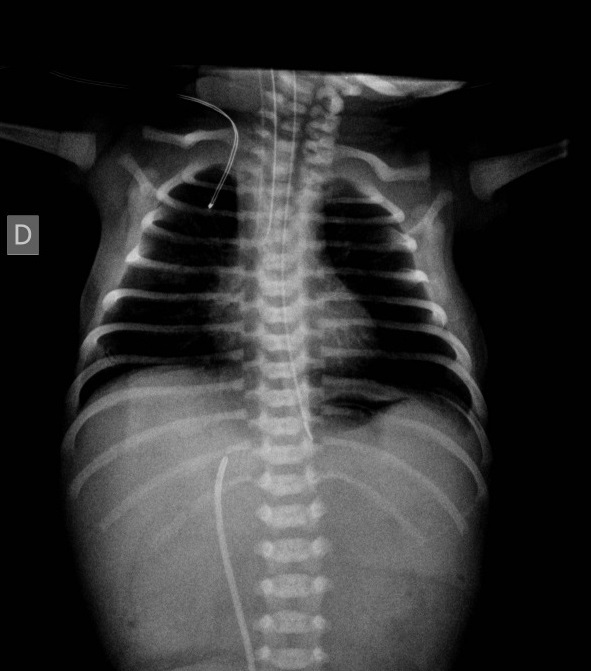

Radiografía al ingreso. Se observa imagen gástrica y total ausencia de aire distal. La sonda nasogástrica ha reducido la distensión gástrica típica de este cuadro. Se observa catéter en vena umbilical.

La atresia de píloro debuta como un cuadro de vómitos alimenticios muy próximos al nacimiento con mínima distensión abdominal en la zona del epigastrio. En la radiografía se observa una única imagen aérea correspondiente al estómago dilatado. No se observa aire distal. Debido a la colocación de la sonda nasogástrica, la dilatación gástrica es pequeña. Consideraciones sobre las obstrucciones intestinales en el periodo neonatal. Los vómitos con o sin intervalo libre de síntomas asociados a polihidramnios en las ecografías prenatales son muy sugestivos de obstrucción a lo largo del tubo digestivo. Las obstrucciones pueden ser intrínsecas: estenosis, atresias o diafragmas, o extrínsecas en caso de vólvulos sobre malrrotaciones de un asa o por compresión externa (páncreas anular, duplicación digestiva). El tratamiento de todas ellas es quirúrgico: